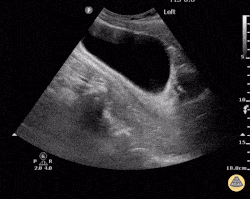

What quadrant are we in?

This is a RUQ view, also known as a right flank view or perihepatic view. The predominant organ in this view is the liver with Morrison's pouch directly below, between the liver and kidney.